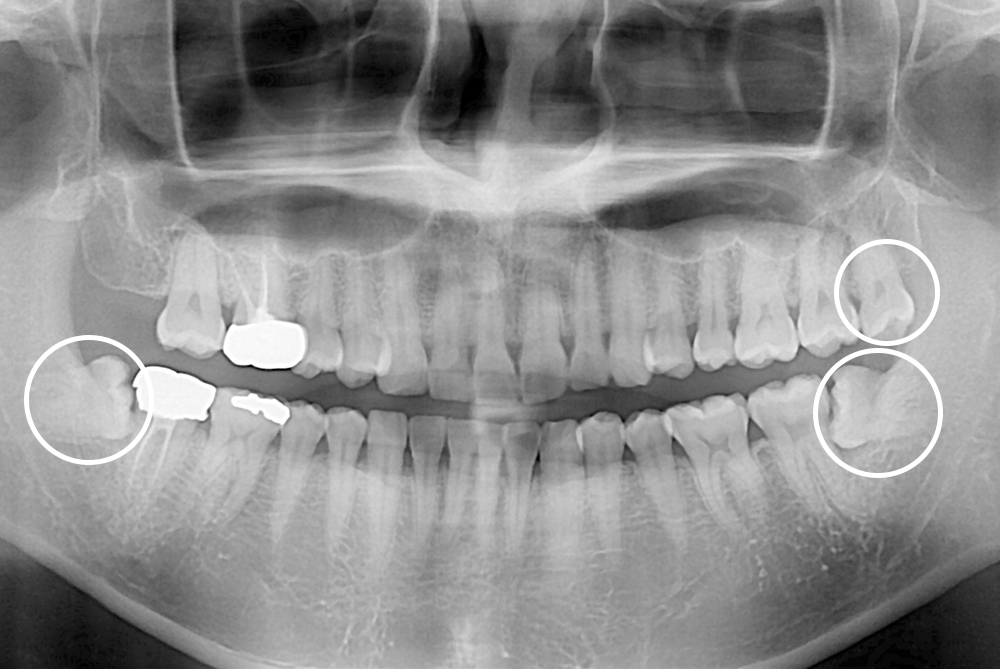

[사랑니] 매복 사랑니 발치

치료전 : 2021-11-04